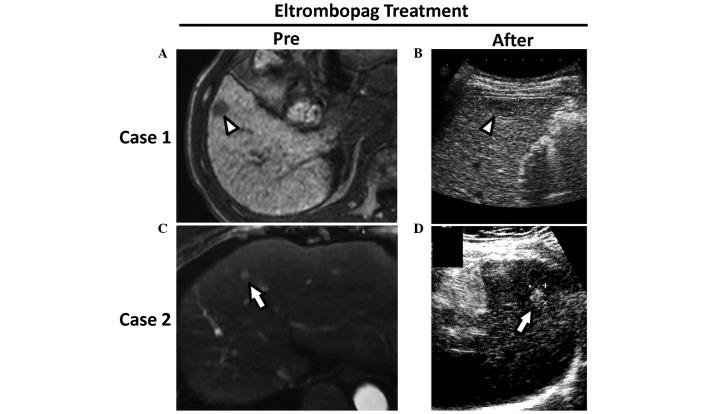

Eltrombopag is an oral thrombopoietin (TPO) receptor agonist that increases platelet counts in patients with idiopathic thrombocytopenic purpura and in patients with liver cirrhosis. When cirrhotic patients with thrombocytopenia undergo elective invasive procedures, eltrombopag treatment reduces the requirement for platelet transfusions. However, TPO is known to have proliferative effects on hepatic progenitor cells and hepatic sinusoidal endothelial cells, which indicates that eltrombopag may accelerate tumor progression. Thus, the effect of eltrombopag on hepatocellular carcinoma (HCC) progression is an important issue. The current study describes two cases of HCC with cirrhosis-related thrombocytopenia. A two-week administration of eltrombopag increased platelet counts from 4.8 to 11.3×10 /μl in case 1 and 4.5 to 23.2×10 /μl in case 2. However, no changes were identified in the serum levels of tumor markers or HCC size following eltrombopag administration in the two cases. These HCCs were curatively treated by radiofrequency ablation without platelet transfusions or serious bleeding. Thus, short-term eltrombopag administration may not accelerate HCC proliferation and may be beneficial for invasive HCC treatment in cirrhotic patients with thrombocytopenia.

艾曲波帕是一种口服血小板生成素(TPO)受体激动剂,可增加特发性血小板减少性紫癜患者和肝硬化患者的血小板计数。当肝硬化伴血小板减少的患者接受择期侵入性操作时,艾曲波帕治疗可减少血小板输注需求。然而,已知TPO对肝祖细胞和肝窦内皮细胞有增殖作用,这表明艾曲波帕可能会加速肿瘤进展。因此,艾曲波帕对肝细胞癌(HCC)进展的影响是一个重要问题。本研究描述了2例伴有肝硬化相关血小板减少的HCC病例。在病例1中,给予艾曲波帕两周后,血小板计数从4.8×10⁹/μl增加至11.3×10⁹/μl,在病例2中从4.5×10⁹/μl增加至23.2×10⁹/μl。然而,在这2例患者中,给予艾曲波帕后,肿瘤标志物血清水平和HCC大小均未发现变化。这些HCC通过射频消融得到了根治性治疗,无需进行血小板输注或出现严重出血。因此,短期给予艾曲波帕可能不会加速HCC增殖,且可能有利于肝硬化伴血小板减少患者的侵入性HCC治疗。